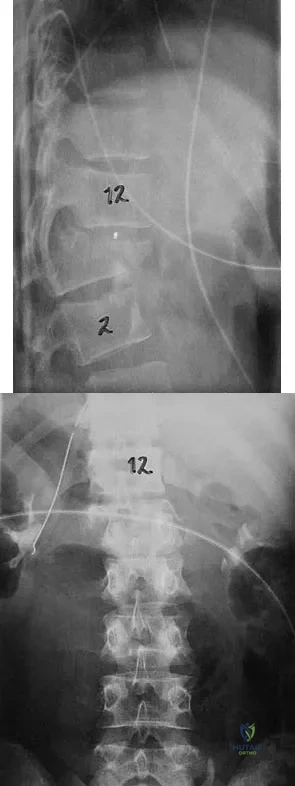

Which of the following factors has the greatest effect on the pull-out strength of a lumbar pedicle screw?

Explanation